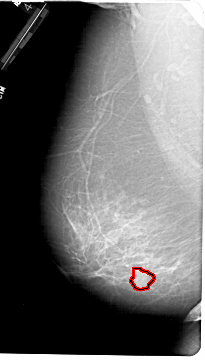

A_1190_1.LEFT_MLO

FILE: A_1190_1.LEFT_MLO.OVERLAY

TOTAL_ABNORMALITIES 1

ABNORMALITY 1

LESION_TYPE MASS SHAPE ROUND MARGINS ILL_DEFINED

ASSESSMENT 4

SUBTLETY 3

PATHOLOGY MALIGNANT

TOTAL_OUTLINES 1

BOUNDARY